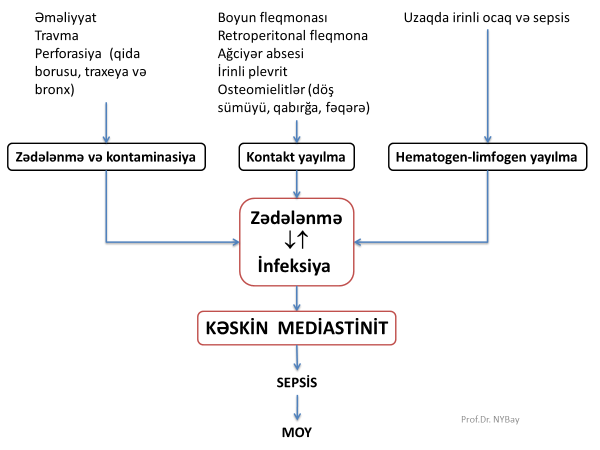

Səbəbləri və patogenezi

Kəskin mediastinit əksər hallarda ikincili xəstəlikdir, başqa sözlə, döş qəfəsi və ya ətraf orqanlarda baş verən zədələnmə və ya irinli iltihabi xəstəliklərin ağırlaşmasıdır (Şəkil 8).

Digər irinli xəstəliklərdə olduğu kimi divararalığında irinli iltihabın baş verməsi üçün iki əsas şərt toxuma zədələnməsi və infeksiyadır. Nekrotik və ya işemik toxuma irinli infeksiyanın inkişafına şərait yaradır. Bir tərəfdən inkişaf edən infeksiya, digər tərəfdən isə nekroza və infeksiyaya cavab kimi ortaya çıxan iltihabi reaksiya yeni zədələnmələrə səbəb olur. Beləliklə, “zədələnmə – irinli infeksiya – zədələnmə” qüsurlu dövranı meydana gəlir və proses proqressivləşir.

Patogenetik baxımdan kəskin mediastinitin səbəblərini 3 qrupda cəmləşdirmək olar:

- kontaminasiya – zədələnmə və infeksiyalaşma nəticəsində meydana gəlir

- birbaşa yayılma – irinli iltihabın divararalığına keçməsi

- distant (uzaqdan) yayılma – hematogen və ya limfogen yayılma

- Kontaminasiya boşluqlu orqanların perforasiyası nəticəsində divararalığının “möhtəviyyatla kirlənməsi” və ya döş boşluğunda aparılan əməliyyatlardan sonrakı irinləmə nəticəsində baş verir. Qida borusunun müayinələr və ya qusma nəticəsində perforasiyası kəskin mediastinitin ən çox rast gəlinən səbəbidir (90%).

- Ətraf orqanlarda baş verən irinli iltihabın divararalığına keçməsi nəticəsində baş verən mediastinitlərə də az rast gəlinmir. Plevra və ağciyərin xəstəlikləri (irinli plevrit, abses), boyun, retroperitoneal fleqmona, qabırğaların, fəqərələrin, döş sümüyünün osteomielitləri divararalığına yayıla bilər.

- Uzaqda yerləşən infektiv ocaqdan hematogen və limfogen yolla yayılan septik embollar divararalığı toxumalarında işemiya-nekroz törədərək kəskin mediastinitə səbəb ola bilərlər.

Şəkil 8. Kəskin mediastinitin səbəbləri və patogenezi